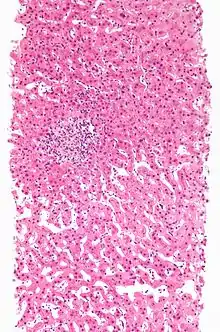

| Drug-induced hepatitis with granulomata. Other causes were excluded with extensive investigations. Liver biopsy. H&E stain. | |

Granuloma

Drug-induced hepatic granulomas are usually associated with granulomas in other tissues and patients typically have features of systemic vasculitis and hypersensitivity. More than 50 drugs have been implicated.

- Causes:

- Allopurinol, phenytoin, isoniazid, quinine, penicillin, quinidine